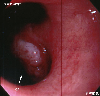

内窥镜

病理学分类恶性上皮肿瘤/类基底细胞癌

病例的种类罕见病例